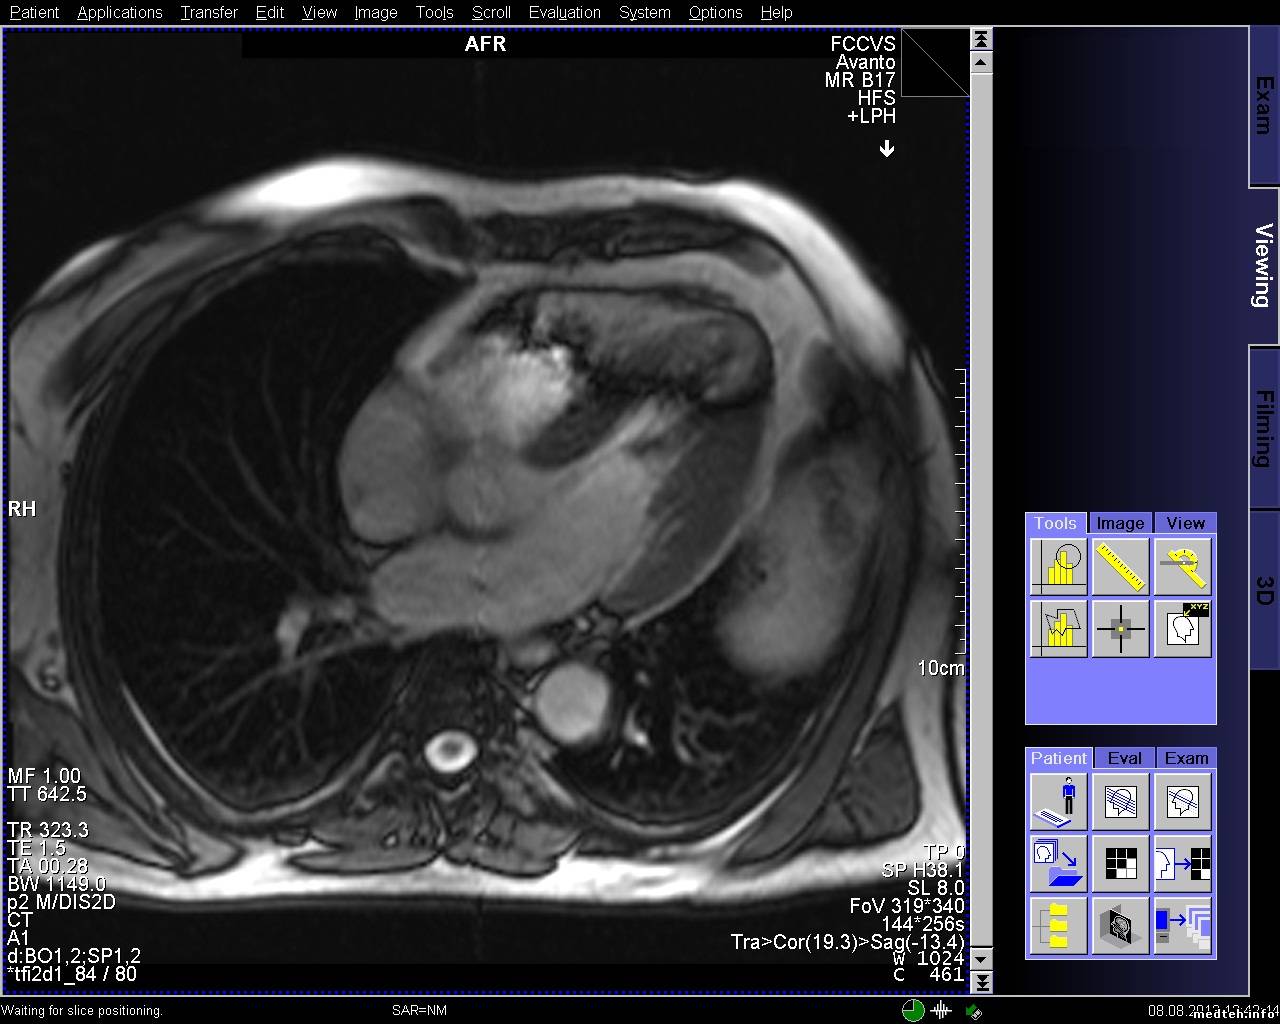

Появились артефакты на изображении при обследованиях сердца. Все тесты качества проходят.

8009364.jpg (263.4 Kb) · 5451893.jpg (273.5 Kb) · 9546723.jpg (256.9 Kb)

FedorM, спайк чек проходит, клетка в норме, источников помех нет, в том числе и светодиодных лампочек (был прецедент давненько). Полосы есть на всех направлениях срезов, но отличаются шириной и положением, могут быть узкие или широкие, могут быть сбоку от основного изображения, могут быть по средине.

FedorM, спайк чек проходит, адвансед спайк чек не проходит. Выключал свет и инъектор, пробовал в разных комбинациях включать, адвансед спайк чек так и не проходит. Полосы появляются при обследовании с контрастом, но один раз было когда смотрели шею и коленку.

Всем доброго времени суток! Проблема с полосой так и остается актуальной. По снимку и протоколу было выяснено, что частота полосы ориентировочно 20-30 кГЦ, что соответствует частоте работы градиентов. Если гонять rf-noise, то помех (полос) не наблюдается. Полосы появляются на адвансед спайк чеке. Тест гоняли только на боди катушке и при этом если просто фантом лежит, то полоса может быть, а может и не быть. Но на паценте полоса стабильно стоит. Если положить на стол длинный провод и погонять адвансед спайк чек на боди катушке, то полоса стабильно проявляется. Следовательно пациент служит как бы антенной. Частота полосы в 20 кГц наводит на мысли, что неисправность в filter plate. Подскажите пожалуйста, что, где и как ещё можно посмотреть и проверить, если неисправность в filter plate, то как его проверить?